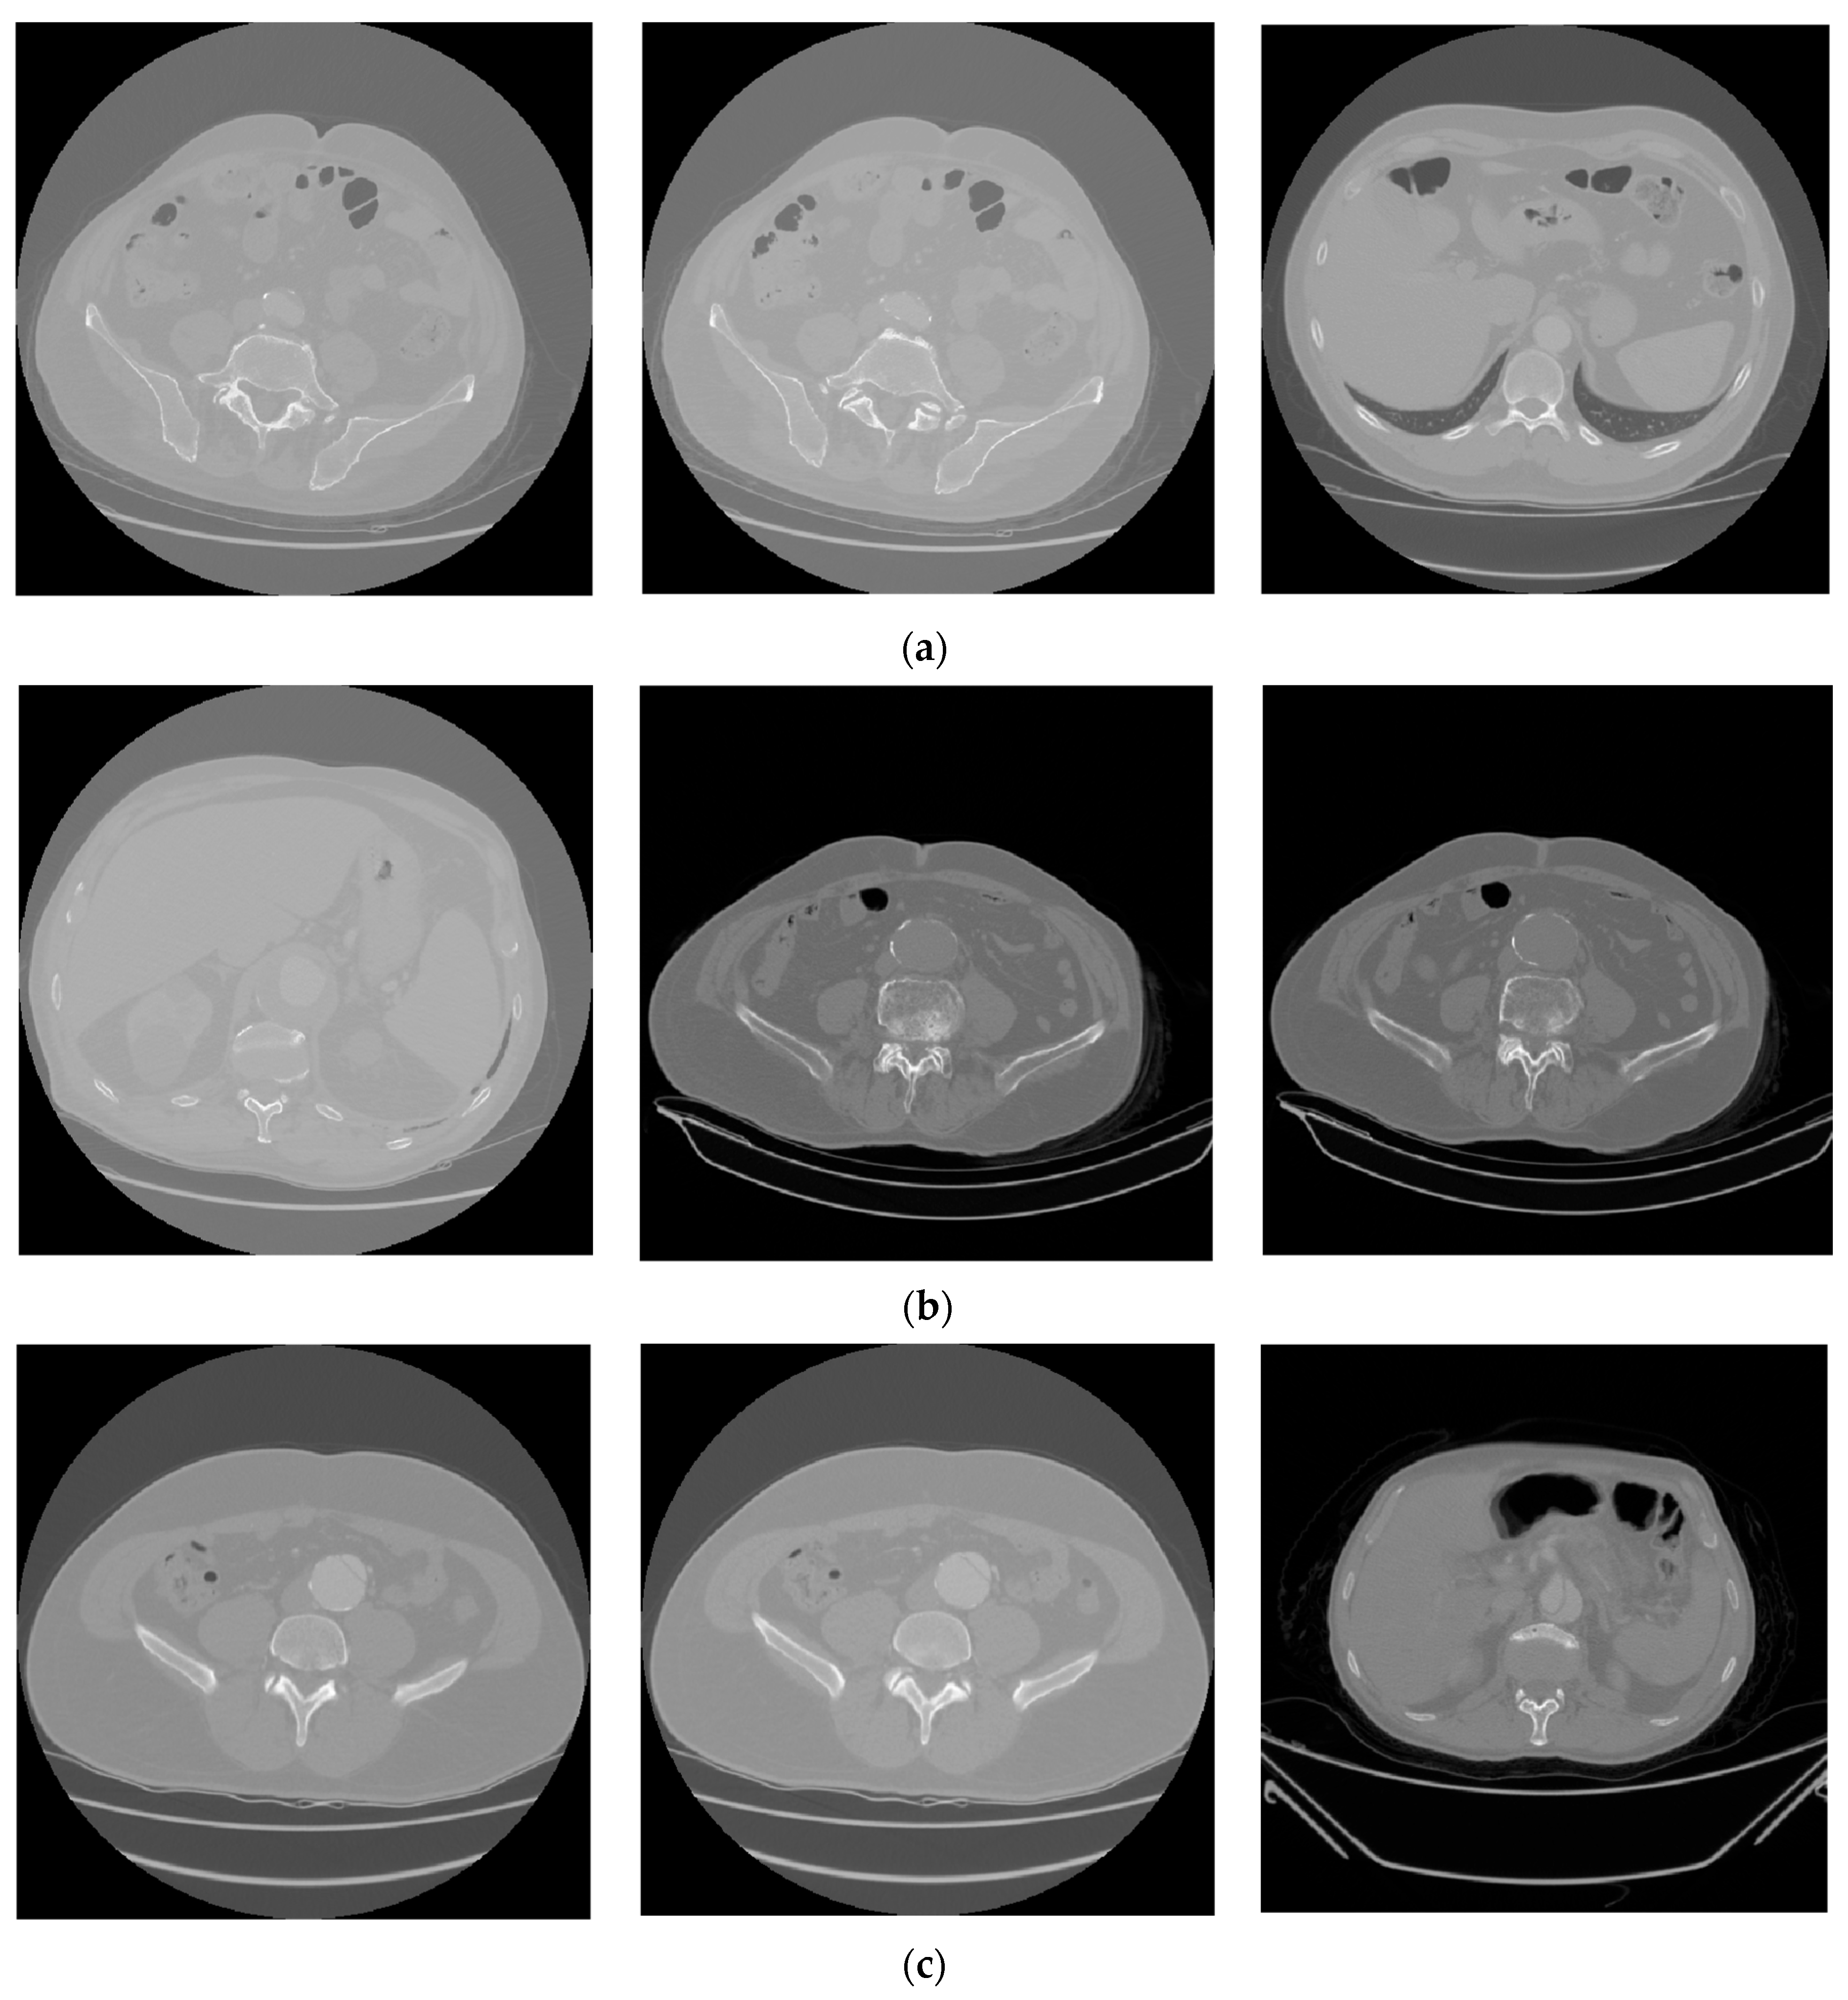

3.1. Dataset

3.3. The Performance Results of the AAA and AAD Diagnosis and Classification